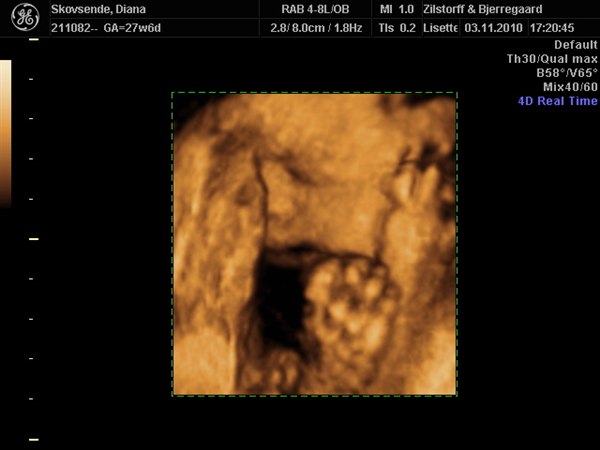

Wauw, hvor er det altså vildt, det man kan se på sådan nogle 3D-billeder. Jeg er vild med nr. 2 billede, der viser hende i profil. Kan I genkende jer selv i det?

Elsker billedet i profil!!!

Profil billedet er bare skøøønt!!

Ja vi er også rigtig glade for profil billed det lykkes hende lige at få hende drejet nok til at kunne tage det.